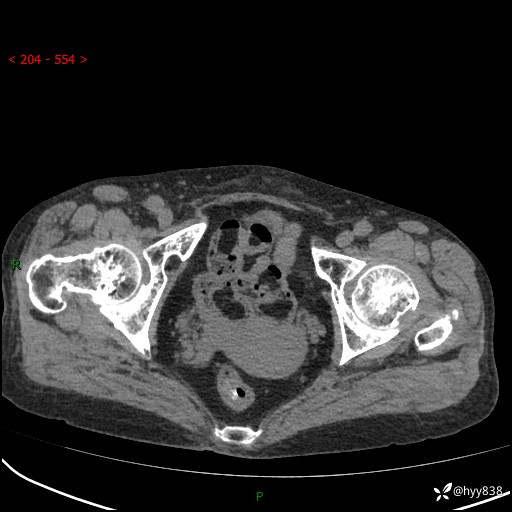

全腹部CT平扫